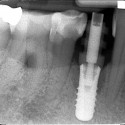

Foto 1: Radiografia della situazione iniziale: il molare mancante

Foto 3: Radiografia di corona e impiantoLa paziente ha perso il primo molare superiore destro (il 16) per carie destruente e problemi endodontici della radice (vedi radiografia).

La terapia d’elezione non è il classico ponte che richiederebbe la limatura dei due denti adiacenti, ma l’impianto endosseo singolo indipendente. In tal modo non si “toccano” i denti adiacenti.

Si inserisce pertanto un impianto endosseo in titanio e dopo un periodo di tre mesi per l’osteointegrazione, a guarigione avvenuta come si vede nella radiografia, si protesizza l’impianto, inserendo un moncone in titanio e cementando una corona in porcellana.